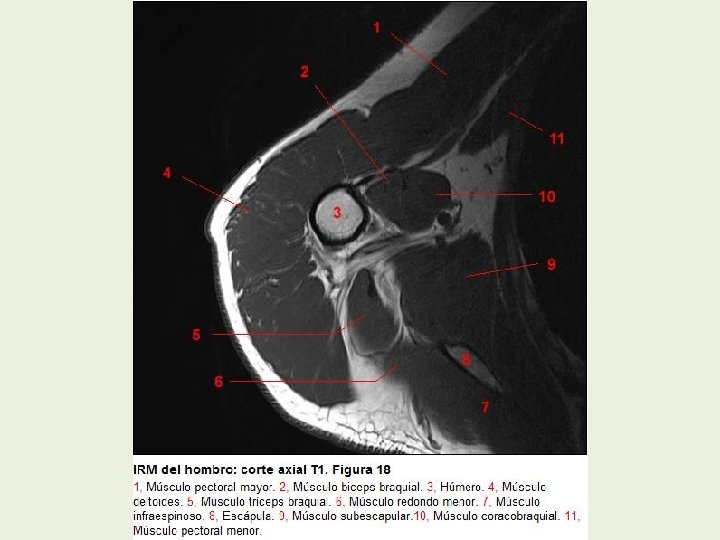

Hombro Cortes axiales RMN